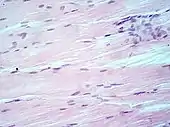

Muscle tissue, cell nuclei (blue-purple), extracellular material (pink).